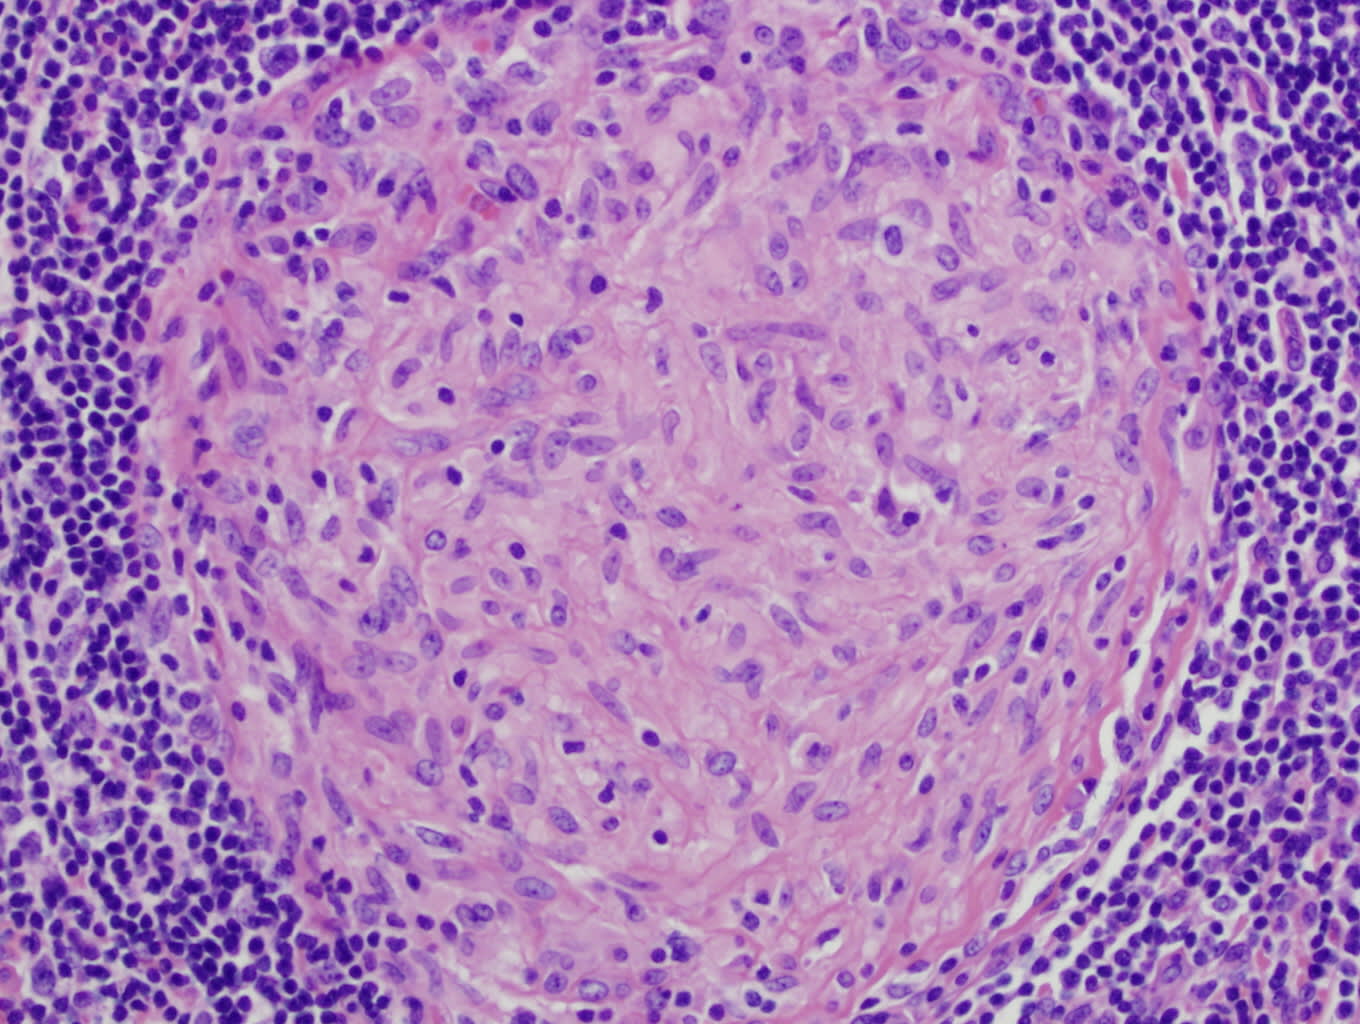

The thick wall around the bacterium isn’t the only barrier to entry for antibiotics, either. The very shape of Mycobacteria also presents a challenge; they look like long rods and cluster together to form “cords.” The bacteria also cluster sideways, thickening the cords, and making it so any bacteria sheltering near the middle of the cluster are shielded from drugs. When M. tuberculosis enters a human cell, large cells called macrophages engulf and break them down, surrounding the pathogens and forming a clump known as a granuloma. Not all pathogens are killed by the macrophages, however, and those that survive within the granuloma’s center fail to be cleared by antibiotics.

A granuloma found inside an infected patient’s lymph node.